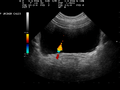

Ultrasound demonstration of ureteral jet effect

Ultrasound demonstration of ureteral jet effect Doppler ultrasound image ureteric jet effect inside urinary bladder.

Doppler ultrasound image ureteric jet effect inside urinary bladder.